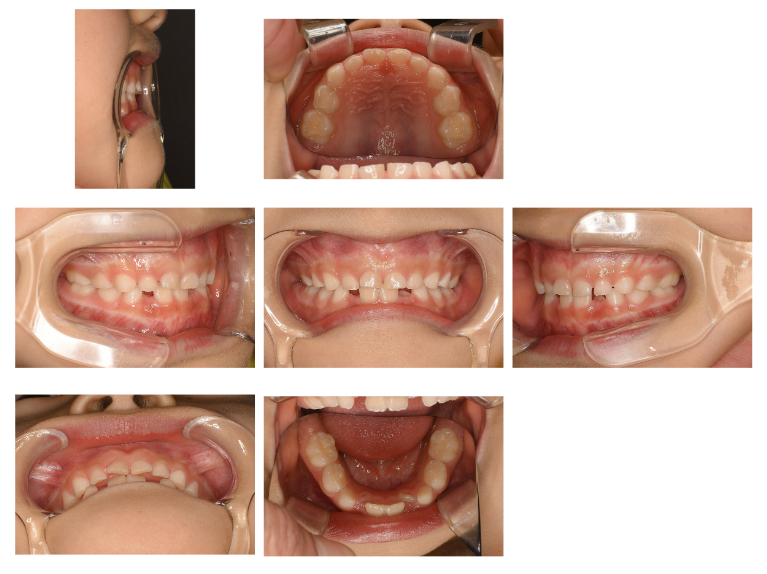

Case1

術前